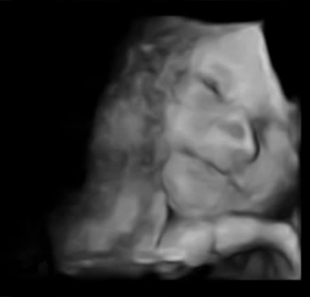

У нас ребенок одной щекой лежал на плаценте и мирно спал. Помогла маленькая шоколадка, благодаря ей он проснулся и все узи нам улыбался, это невероятные ощущения!

Показываю что у нас получилось, срок 27 недель и 3 дня

Такие полные губы =D Интересно еще то, что у всех детей в 3d крупноват нос, не знаю с чем это связанно, может быть кто-то еще замечал?

А это улыбка и приоткрытый глаз =D